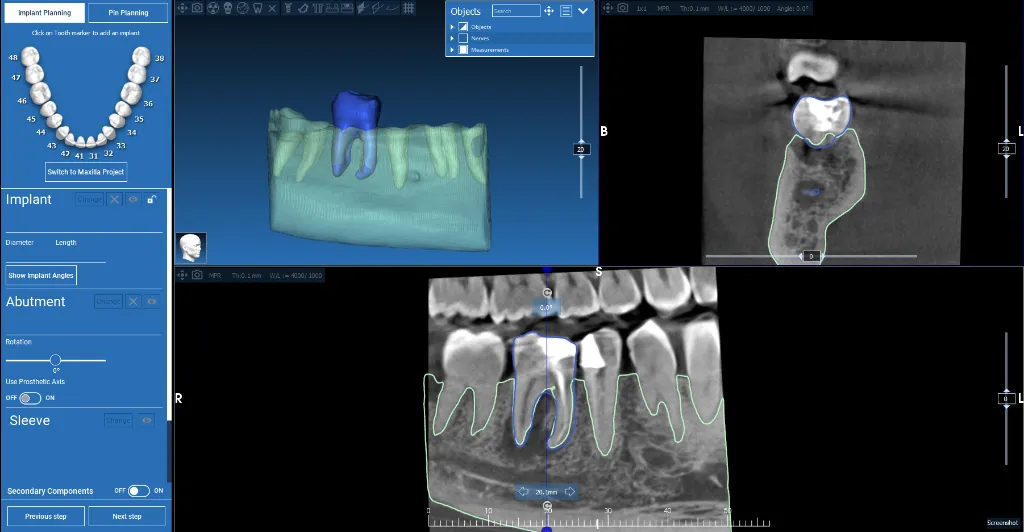

Maxillary Implant Case — 3 Implants

Tooth-supported guide for 3 implants in the upper jaw. Digital planning with precise implant positioning.